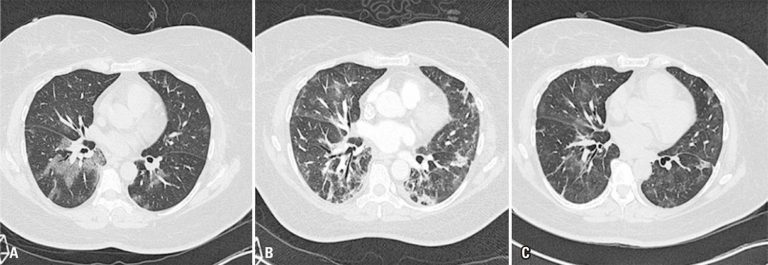

Evolução temporal dos achados tomográficos da infecção pulmonar na COVID-19

Com muito entusiasmo, lemos o excelente artigo de revisão intitulado “Achados da COVID-19 identificados na tomografia computadorizada de tórax”, de autoria de Rosa et al.,() publicado no último número desta revista. O referido trabalho ilustra com casos didaticamente apresentados a importância da tomografia computadorizada (TC) de tórax na detecção das manifestações pulmonares da doença pelo coronavírus 2019 (COVID-19), sem discutir seu papel no seguimento evolutivo da doença. Embora saibamos não ter sido este um escopo dos autores, gostaríamos de complementar essa discussão com alguns pontos referentes ao impacto desse método no prognóstico e na evolução (sobretudo a longo prazo) da COVID-19.